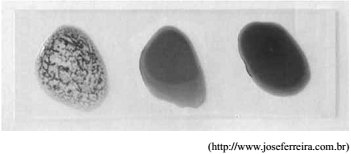

A figura ilustra uma tipagem sanguínea humana, na qual três gotas de sangue foram colocadas em contato com anticorpos anti-A, anti-B e anti-Rh, posicionados da esquerda para a direita na lâmina, conforme a figura.

Foi verificada reação apenas com o anticorpo anti-A, o que confere à pessoa testada sangue tipo A Rh-.

A reação observada durante a tipagem sanguínea é uma reação de_______________ de hemácias, em que______________ da membrana celular da hemácia reagem especificamente com_____________ presentes na lâmina teste.

Assinale a alterativa que completa, correta e respectivamente, as lacunas do parágrafo anterior.